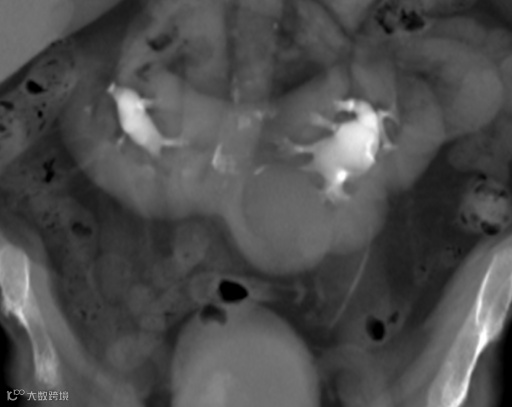

马蹄肾合并左侧下腔静脉。双肾下极融合,双侧肾盂旁多发囊肿,下腔静脉(IVC)在肠系膜上动脉(SMA)起始部走形于主动脉左侧。